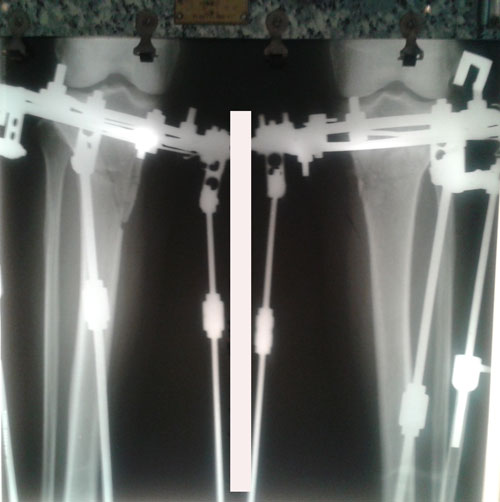

Рентген до операции.

Ножки на сращении.

РЕНТГЕН В 61 ДЕНЬ